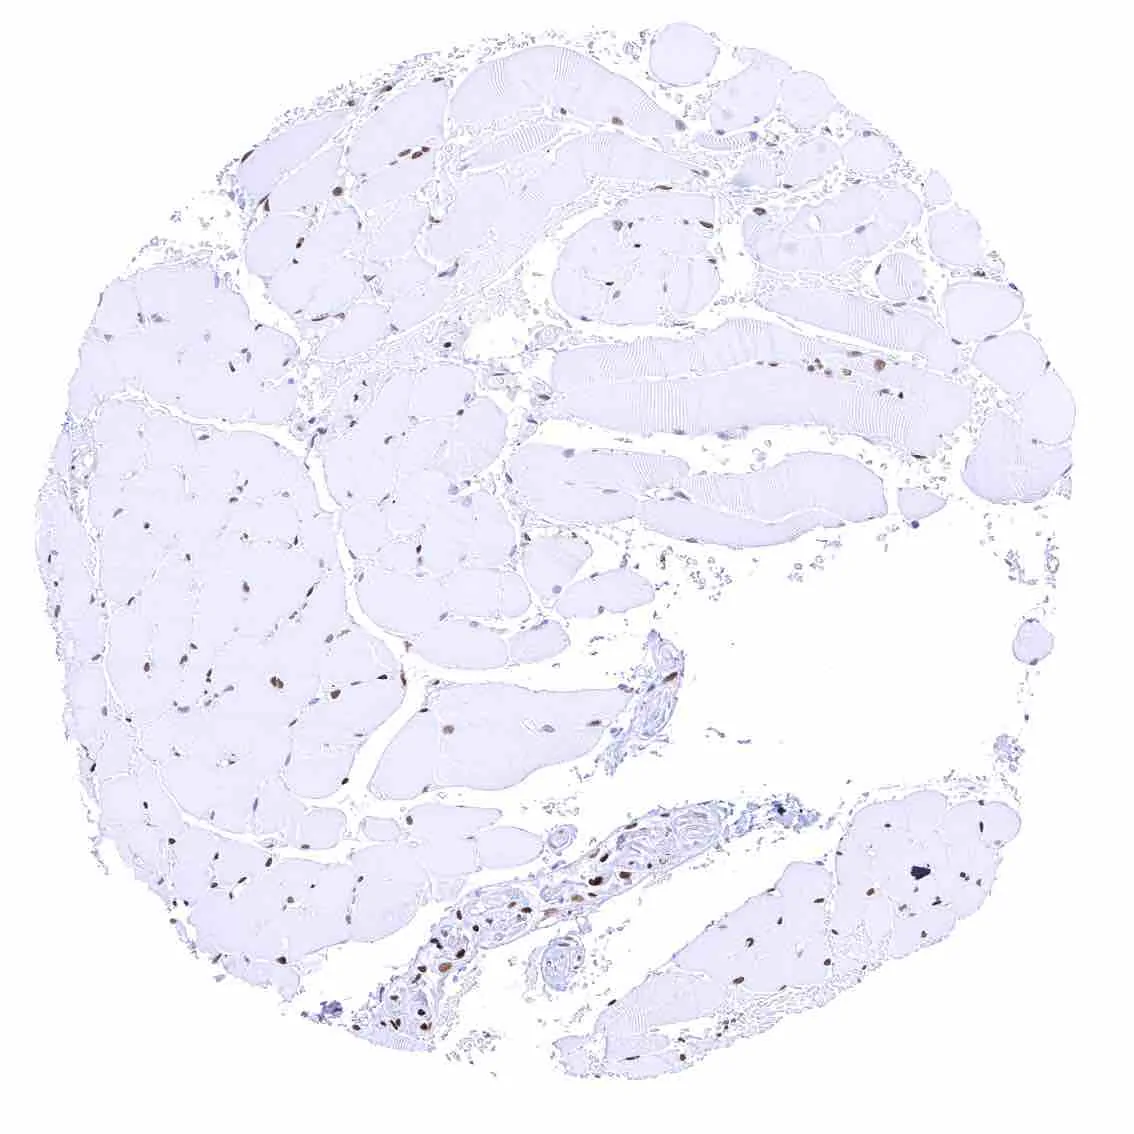

Thyroid gland – Weak to moderate nuclear p27 positivity of most follicular cells.